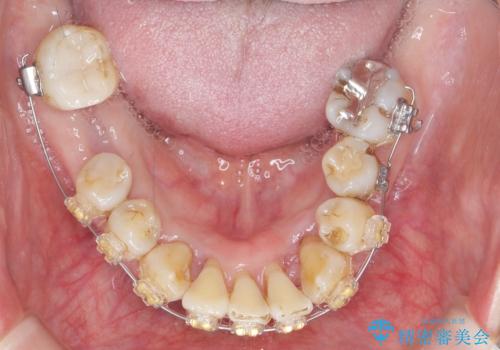

歯周病 、インプラント、 矯正 全顎治療

- 重度の歯周病に罹患しており、他院で「多数の歯を抜歯したのち、入れ歯を入れるしかない。」と言われ、入れ歯以外の方法がないか相談のため来院されました。

重度の歯周病で多数の歯を残せない問題、歯並び・噛み合わせの問題、欠損の問題、と多数の大きな問題が認められました。

このままの歯並びでは仮にインプラントを埋入したとしても歯ブラシがしづらく、また歯周病の問題が再発しやすい、と判断し矯正治療を行ったのちに歯周病治療、インプラント治療を行っていく治療計画としました。

インプラント治療に加え、歯周病に対しての再生治療や歯周ポケットの除去を行う歯周外科、矯正治療、と必要な治療は多岐に渡りましたが、最終的に安定した噛み合わせを得られたとともに、清掃のしやすい口腔内環境を確立できました。